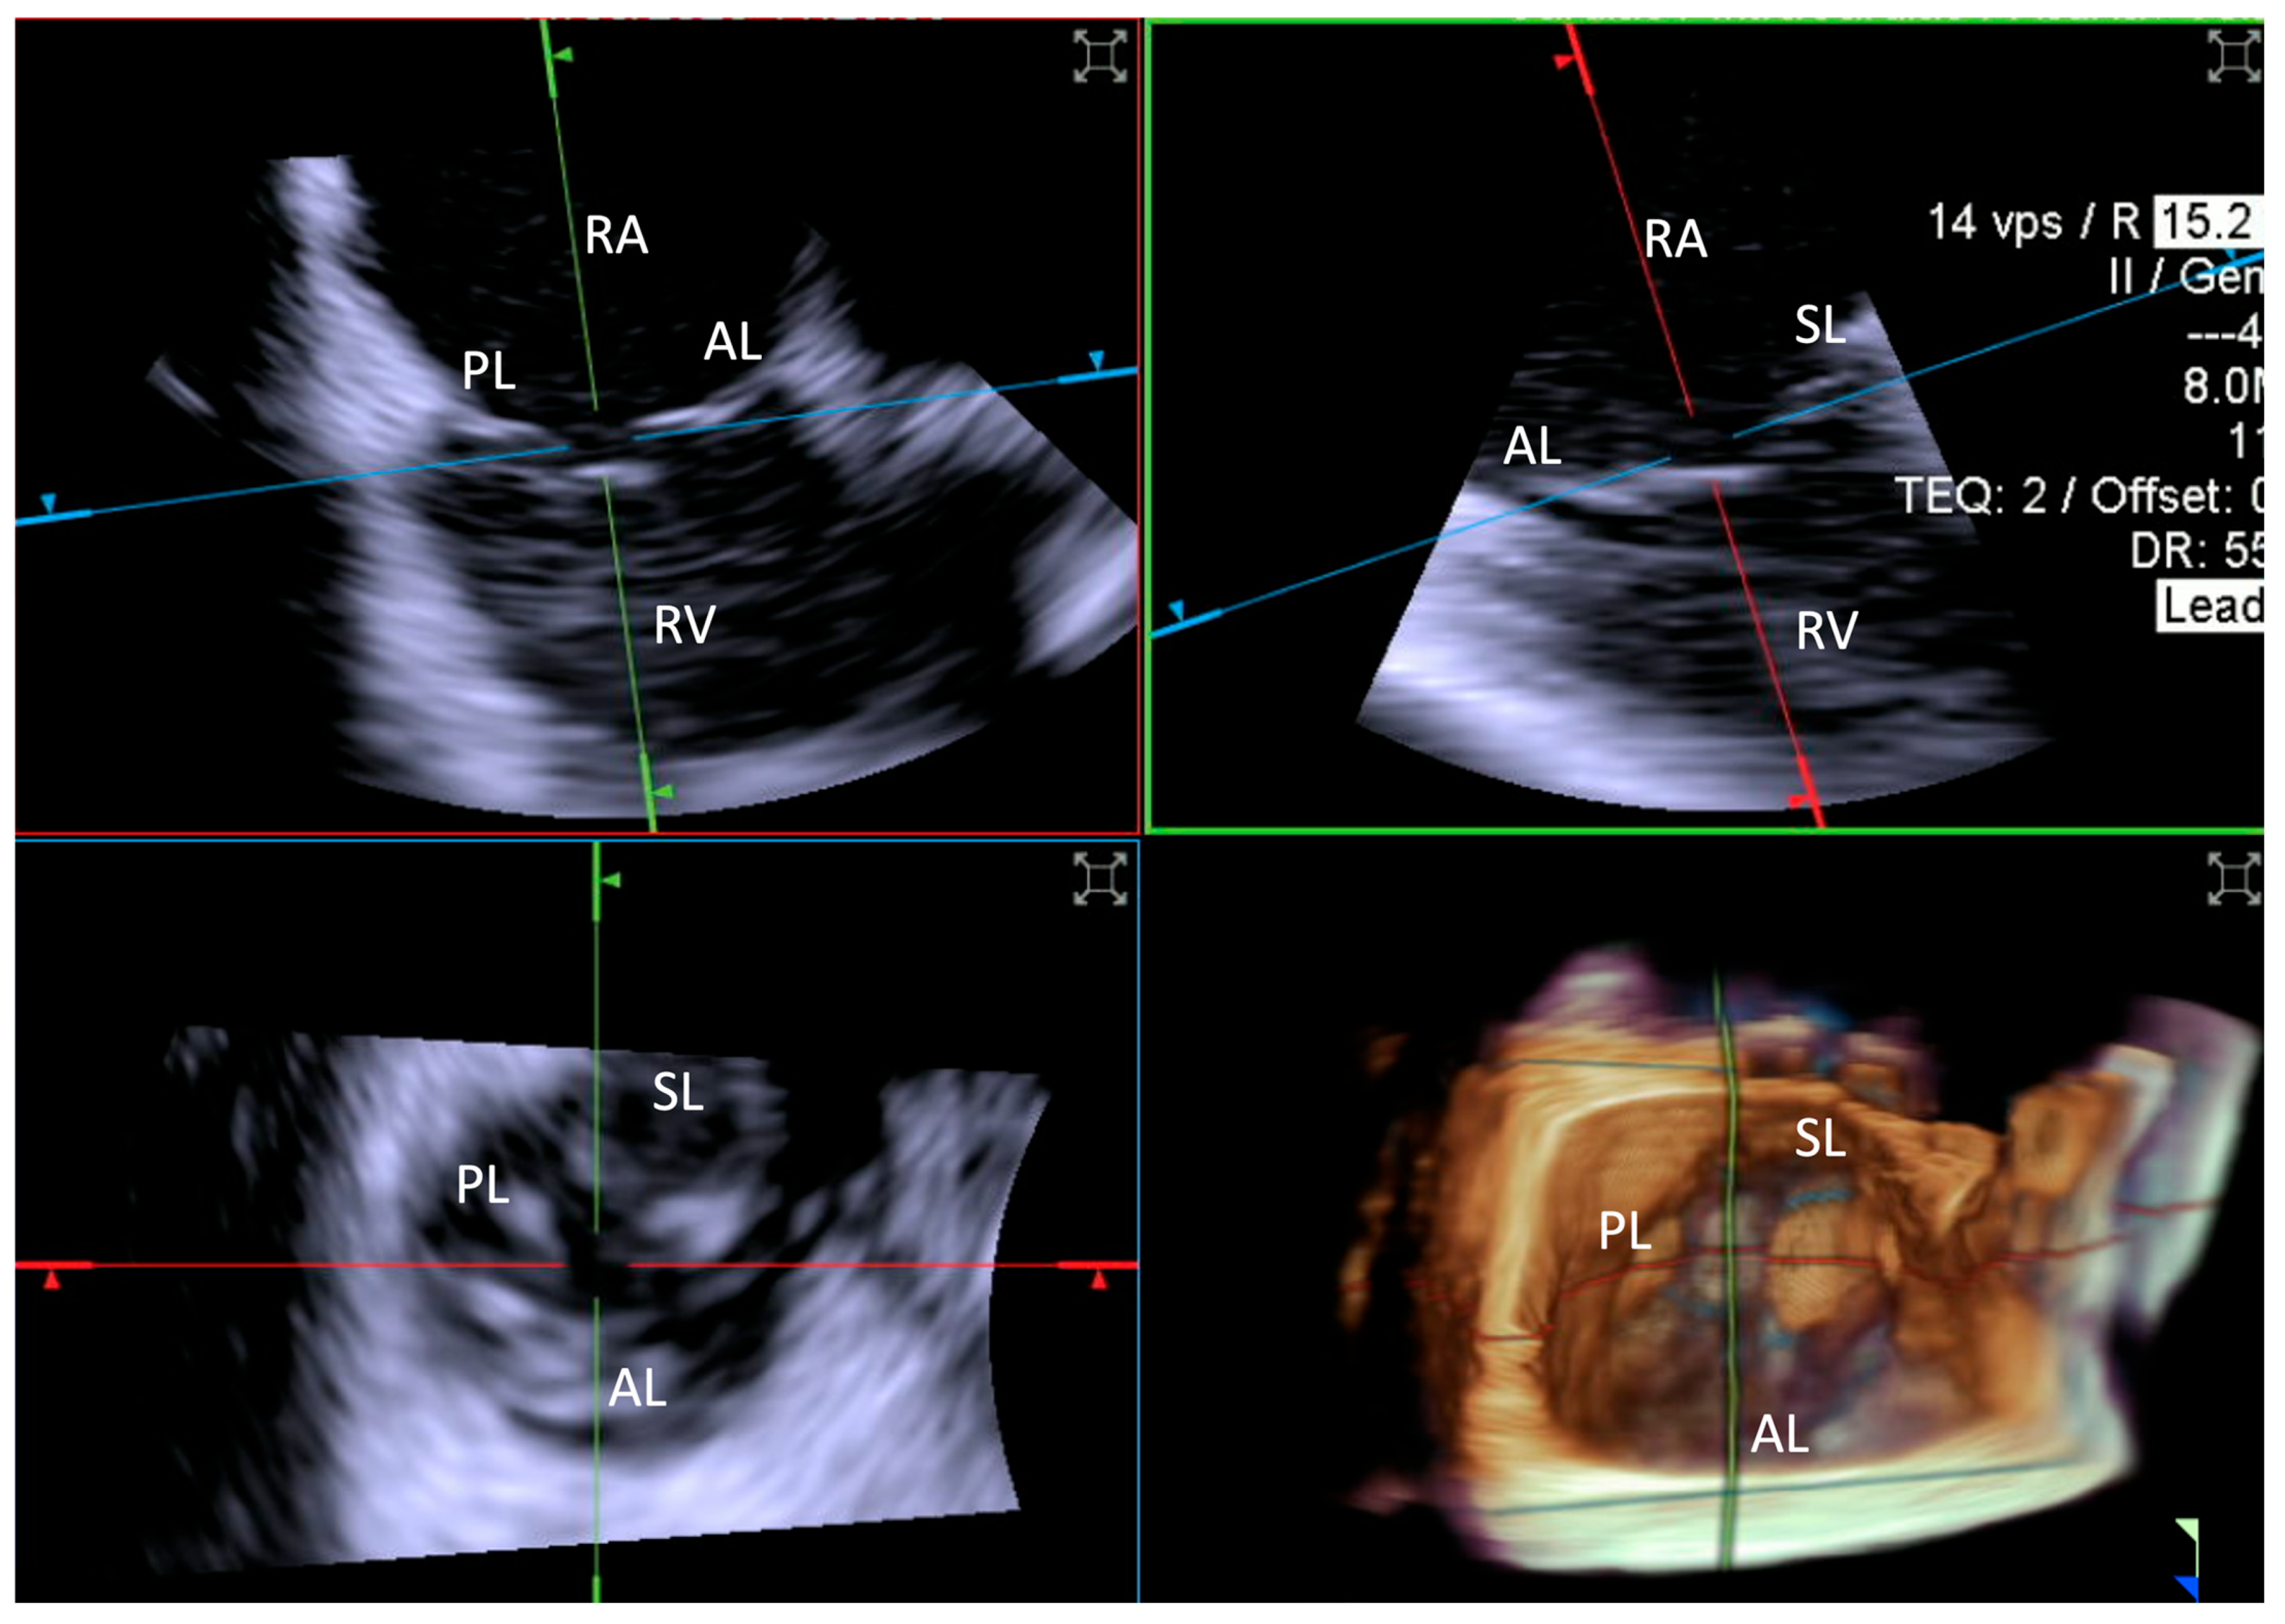

- Step number 1: assessment of tricuspid valve anatomy.

- -

- Step number 2: identification of the target lesion.